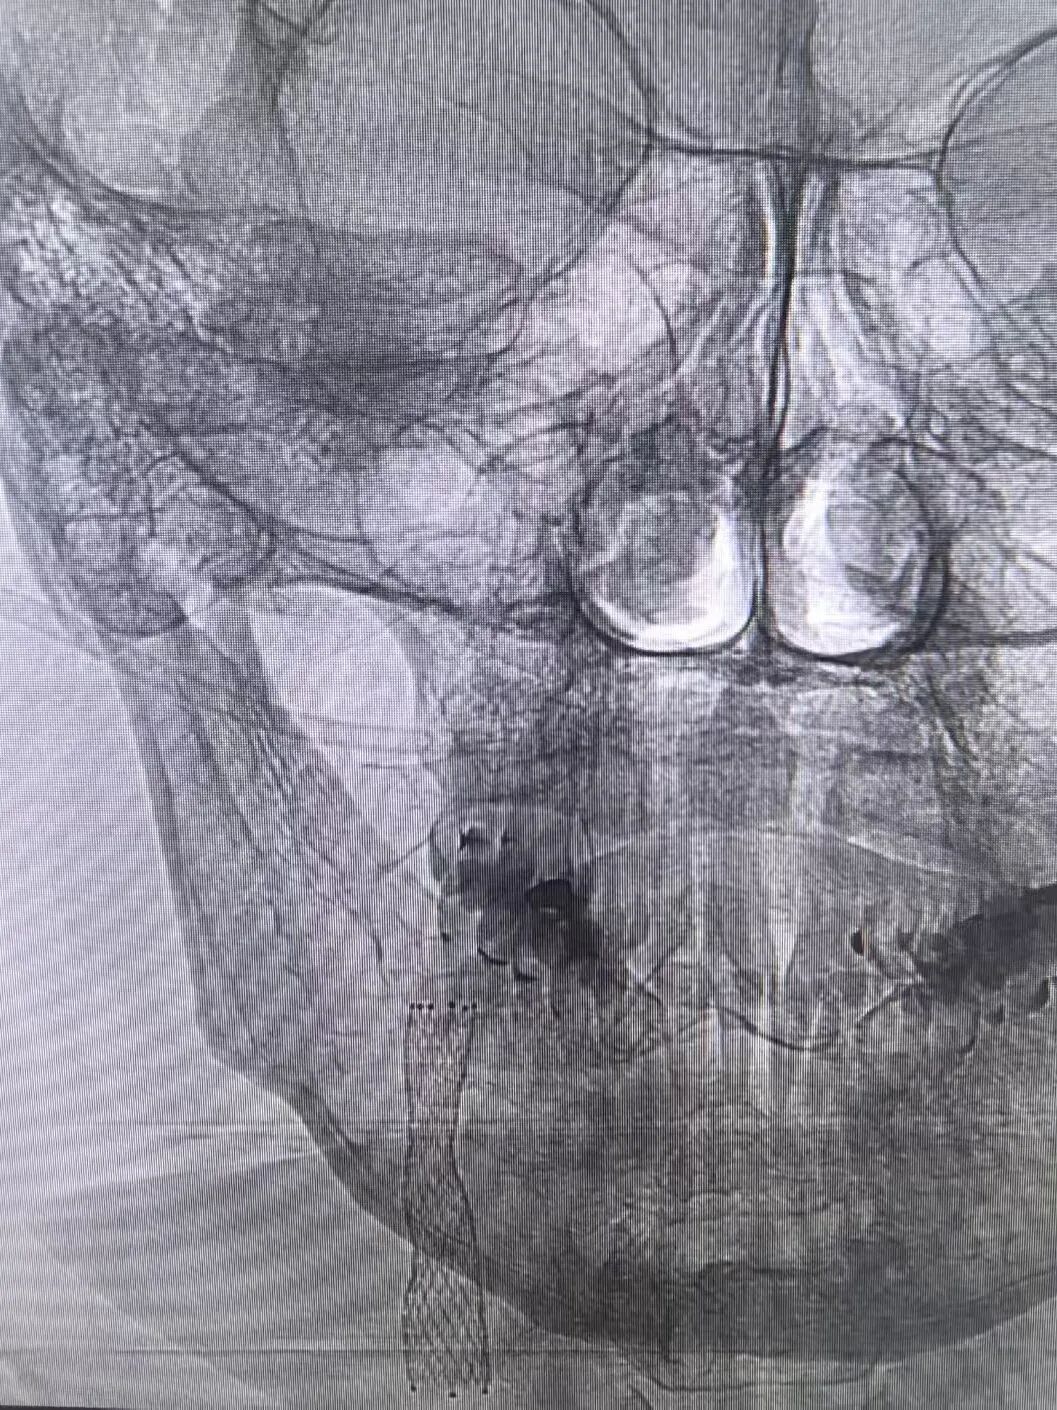

心脏问题刚解决,脑部危机便接踵而至。医疗团队迅速为罗先生实施脑动脉造影,结果显示其右侧颈内动脉近段狭窄达99%。然而心脏术后需维持稍高血压保障心功能,颈动脉支架手术却要求严控血压以规避脑出血风险——两种治疗需求如同天平的两端,在罗先生体内形成了棘手的治疗矛盾。手术团队经过反复研讨、全面评估,与家属进行了充分沟通,决定暂缓脑部手术,给予患者充分的恢复时间,待身体条件达到最佳状态后,再实施颈动脉支架植入手术。

同时,王和平教授紧急到院,带领诊疗团队采用股动脉穿刺微创通路,在DSA引导下精准植入支架,40分钟内解除颈动脉闭塞,造影显示颈动脉血流恢复通畅,术后次日患者即可下床活动。

DSA显示罗先生颈动脉闭塞

置入支架术后影像